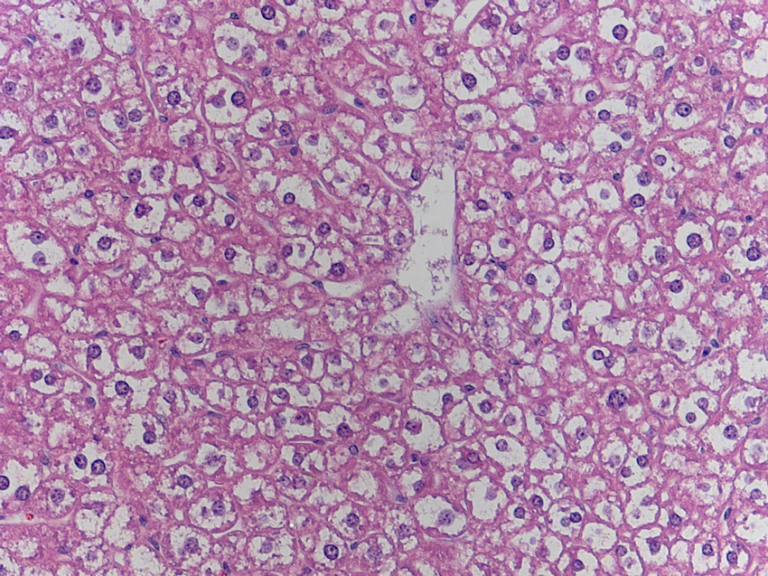

Liver Cells:

Actually, (I realized this after I made the labeled photos) in the top photo here, the white spot is NOT a central vein, because that photo is taken with higher magnification than the very first photo. The white spot is probably a smaller vein or one of the sinusoids labeled in the first picture.

liver cells found in my slides:

This is pretty blurry, but I think this is about the same magnification as the very first picture. This is the only one that I could find so far. I will keep looking.